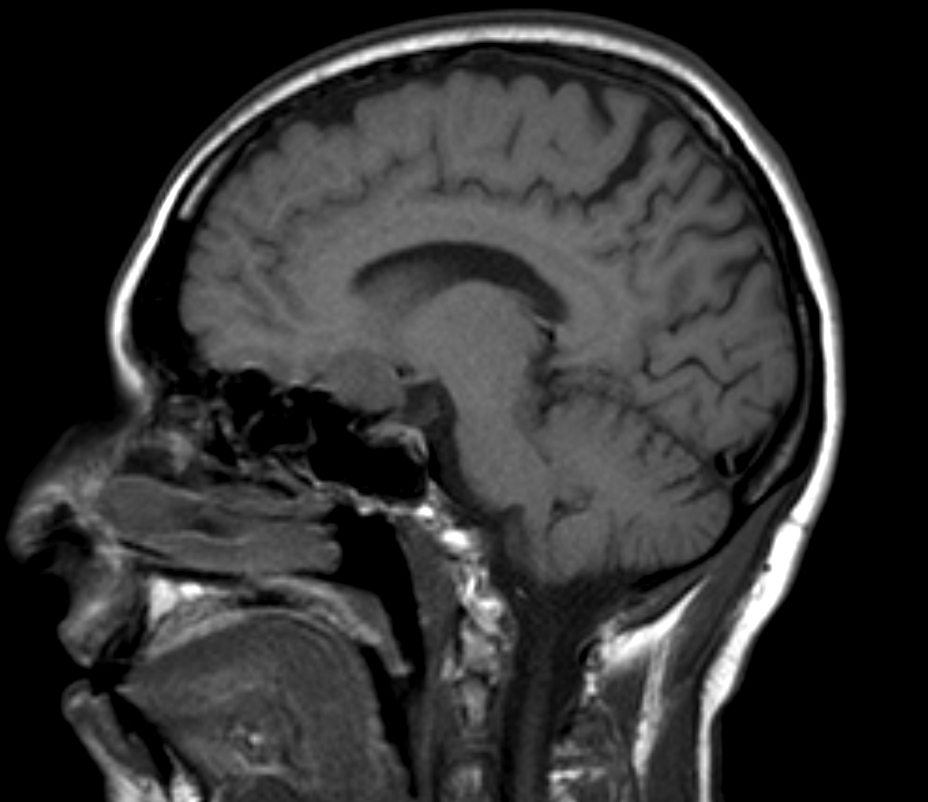

- At MRI, chordoid meningioma is hypoisointense on T1 weighted images and hyperintense on T2 and FLAIR, with contrast enhancement varying from homogeneous to heterogeneous (J Neurooncol 2018;137:575, Neuroradiology 2022;64:253)

- Contrast enhancement is more intense than in meningothelial, transitional or fibrous meningiomas (Neuroradiology 2022;64:253)

- Multicystic appearance is seen in some cases (Neuroradiology 2022;64:253)